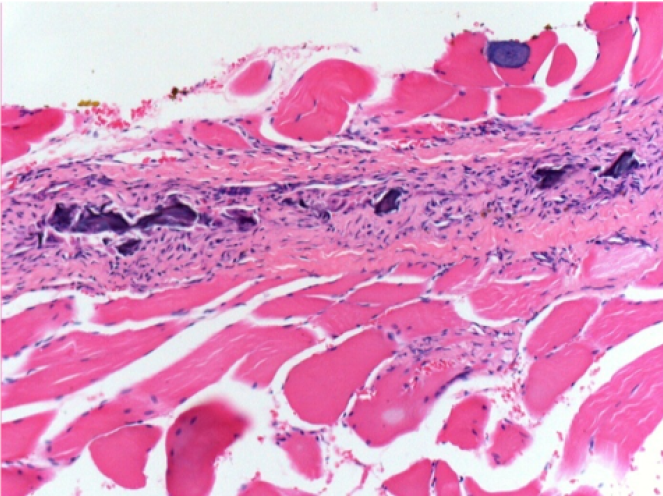

10 days after Endopeel Injection 0.1ml in the right pretibial muscle.

Here you may see the formation of the vacuoles which are surrounded by lymphocytes. Vacuoles are different from tissue necrosis . The presence of lymphocytes is related to the permeability of the cell membranes.

What is seen in black on the pictures is not a necrosis like could imagine some scientifics !

In fact, 4 conclusions have to be taken in consideration